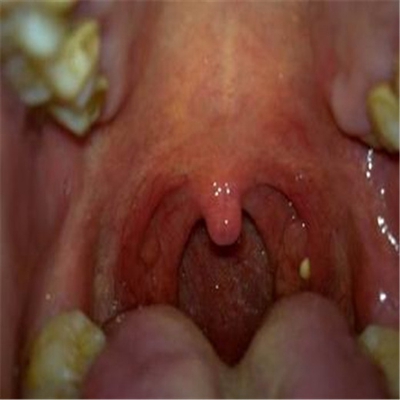

扁桃體惡性腫瘤圖片

扁桃體癌圖 (8)